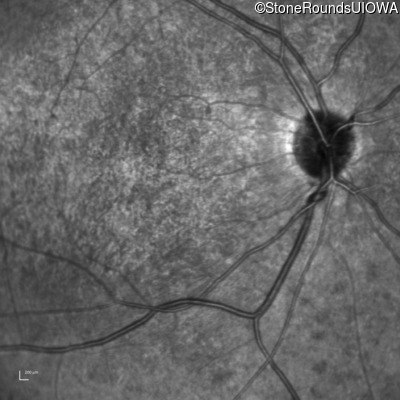

Infrared Fundus Photograph - Left - 20/200 -2 sc

Exemplar